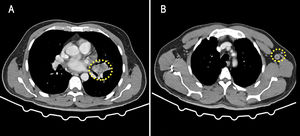

Se presenta el caso de un hombre de 64 años que consultó por malestar general, pérdida del equilibrio y anorexia. No explicaba cefalea, fiebre u otros síntomas. No tenía antecedentes médicos ni hábitos tóxicos destacables. En la exploración física destacó dismetría y marcha lenta e inestable. El examen de fondo de ojo fue normal. Analíticamente presentaba proteína C reactiva elevada (59,63 mg/l) sin leucocitosis. La radiografía de tórax y el electrocardiograma no mostraron hallazgos. La tomografía computarizada craneal reveló múltiples lesiones nodulares con realce difuso en anillo, de distribución en el cerebelo y el parénquima cerebral, con edema perilesional (fig. 1). Se inició dexametasona y el estudio en medicina interna. Los marcadores tumorales y las serologías realizadas (VIH, VHC, VHB, Treponema pallidum, citomegalovirus y toxoplasma) fueron negativos. La tomografía computarizada toracoabdominal mostró 2 tumoraciones parahiliares izquierdas sospechosas (fig. 2A) y adenomegalias mediastínicas y axilares (fig. 2B). La broncoscopia fue normal y no se encontraron células malignas en el lavado broncoalveolar. La biopsia de un ganglio axilar izquierdo evidenció granulomas epitelioides con células gigantes multinucleadas tipo Langerhans y necrosis caseificante central. Se inició el tratamiento empírico con isoniazida, rifampicina, etambutol y pirazinamida. Posteriormente, se aisló Mycobacterium tuberculosis en el cultivo del lavado broncoalveolar, no así en el líquido cefalorraquídeo. El ensayo de liberación de interferón gamma (IGRA) fue positivo y los hemocultivos fueron negativos. A las 3 semanas del tratamiento se observó la mejoría radiológica (fig. 3). El paciente completó 9 meses de tratamiento y alcanzó la curación.